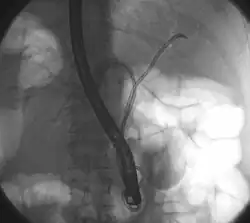

Klatskin tumor during ERCP. Wires were inserted into the left and right biliary systems. Both parts were injected through a tube with contrast, but there is no contrast visible in the area of confluence of the two systems